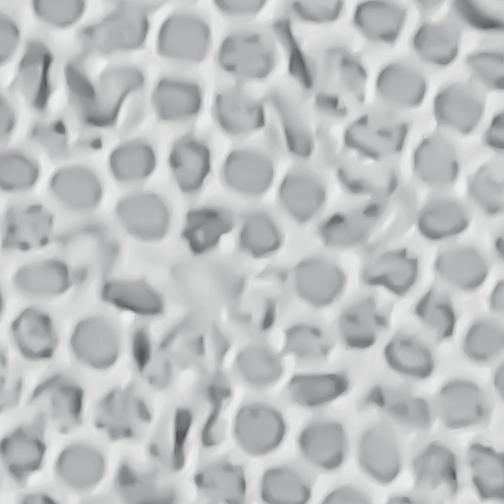

“Ik denk dat die onwetendheid voor veel mensen geldt, ook voor mij. Maar tegelijkertijd is dat ook de uitdaging, want er zijn toch veel mensen die worstelen met sikkelcelziekte. Hoewel ik geen arts ben, weet ik dat het te maken heeft met chronische bloedarmoede. De rode bloedcellen hebben de vorm van een sikkel, een soort halve maan. Daar komt ook de naam vandaan. De rode bloedcellen krijgen bij sikkelcelpatiënten de vorm van een halve maan en verstoppen dan bloedvaatjes. Dat zorgt voor veel pijn. Daarnaast beschadigen ook organen, zoals het hart, de nieren en de longen. De levensverwachting is gemiddeld dertig jaar korter.”